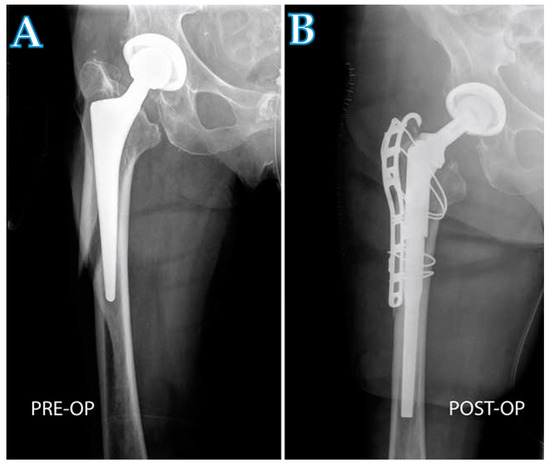

Femoral Revision Total Hip Arthroplasty Performed through the Interval of the Direct Anterior Approach

2.1. Surgical Technique